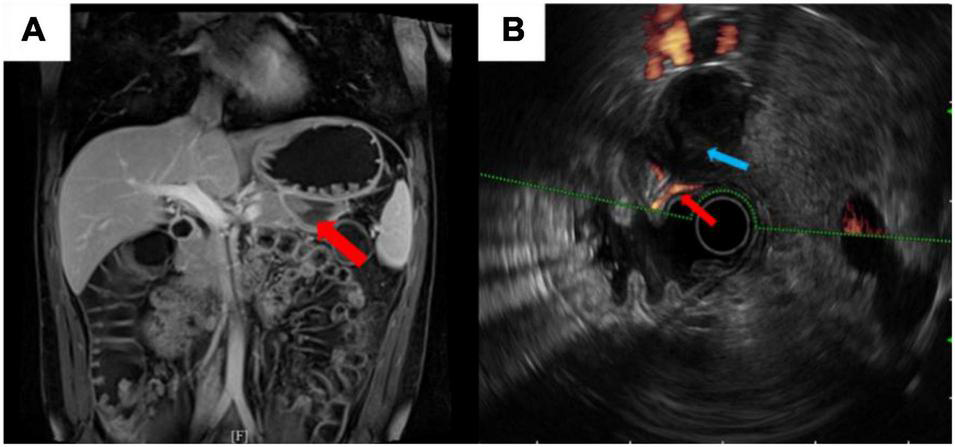

To clarify the reason for the hemorrhage, enhanced magnetic resonance imaging (MRI) was performed, which revealed a hematoma in the gastro-pancreatic gap, without signs of space-occupying lesion and other indications about the source of bleeding (Figure 2A). Later, we performed endoscopic ultrasonography (EUS) on him. A mixed hypoechoic and anechoic lesion was seen between the pancreatic tail and the gastric wall, which was closely related to the peripheral blood vessels and was considered to be a hematoma combined with the previous imaging reports. Part of the muscularis propria was connected to the hematoma. In addition, Doppler ultrasonography showed that the blood flow signal was continuous between the muscularis propria and hematoma, which was considered as the vascular malformation in the muscularis of the stomach (Figure 2B). He was ultimately diagnosed with “intraperitoneal hemorrhage due to VMs in the muscularis of the stomach” based on the CT images and the EUS results, combined with the clinical manifestation. The patient was young and had fertility demands shortly. He was reluctant to accept CTA and interventional therapy due to the radiation dose of CTA and endovascular treatment. Also, considering that no obvious bleeding site was found on enhanced CT, we were concerned that the intervention would not be able to locate the lesion, so we did not conduct invasive treatment, such as endovascular management or surgery. The patient recovered gradually after conservative treatment without signs of continuous bleeding, and he was discharged after 4 days (the final laboratory data are shown in Table 1). We performed follow-ups for the patient at the hospital outpatient department at 6 months intervals. The follow-up after 1 year showed that the patient had no signs of recurrence (Figure 3). The timeline from emergency to follow-up is presented in Figure 3.

FIGURE 2

(A) Enhanced magnetic resonance imaging (MRI) revealed no sign of space-occupying lesion. Red arrow showed a hematoma in the gastro-pancreatic gap. (B) Endoscopic ultrasonography (EUS) illustrated the vascular malformation in the muscularis of the stomach. Blue arrow showed a hypoechoic shadow. Red arrow showed a 1.3-mm diameter blood flow signal was continuous between the muscularis propria and the hypoechoic shadow.